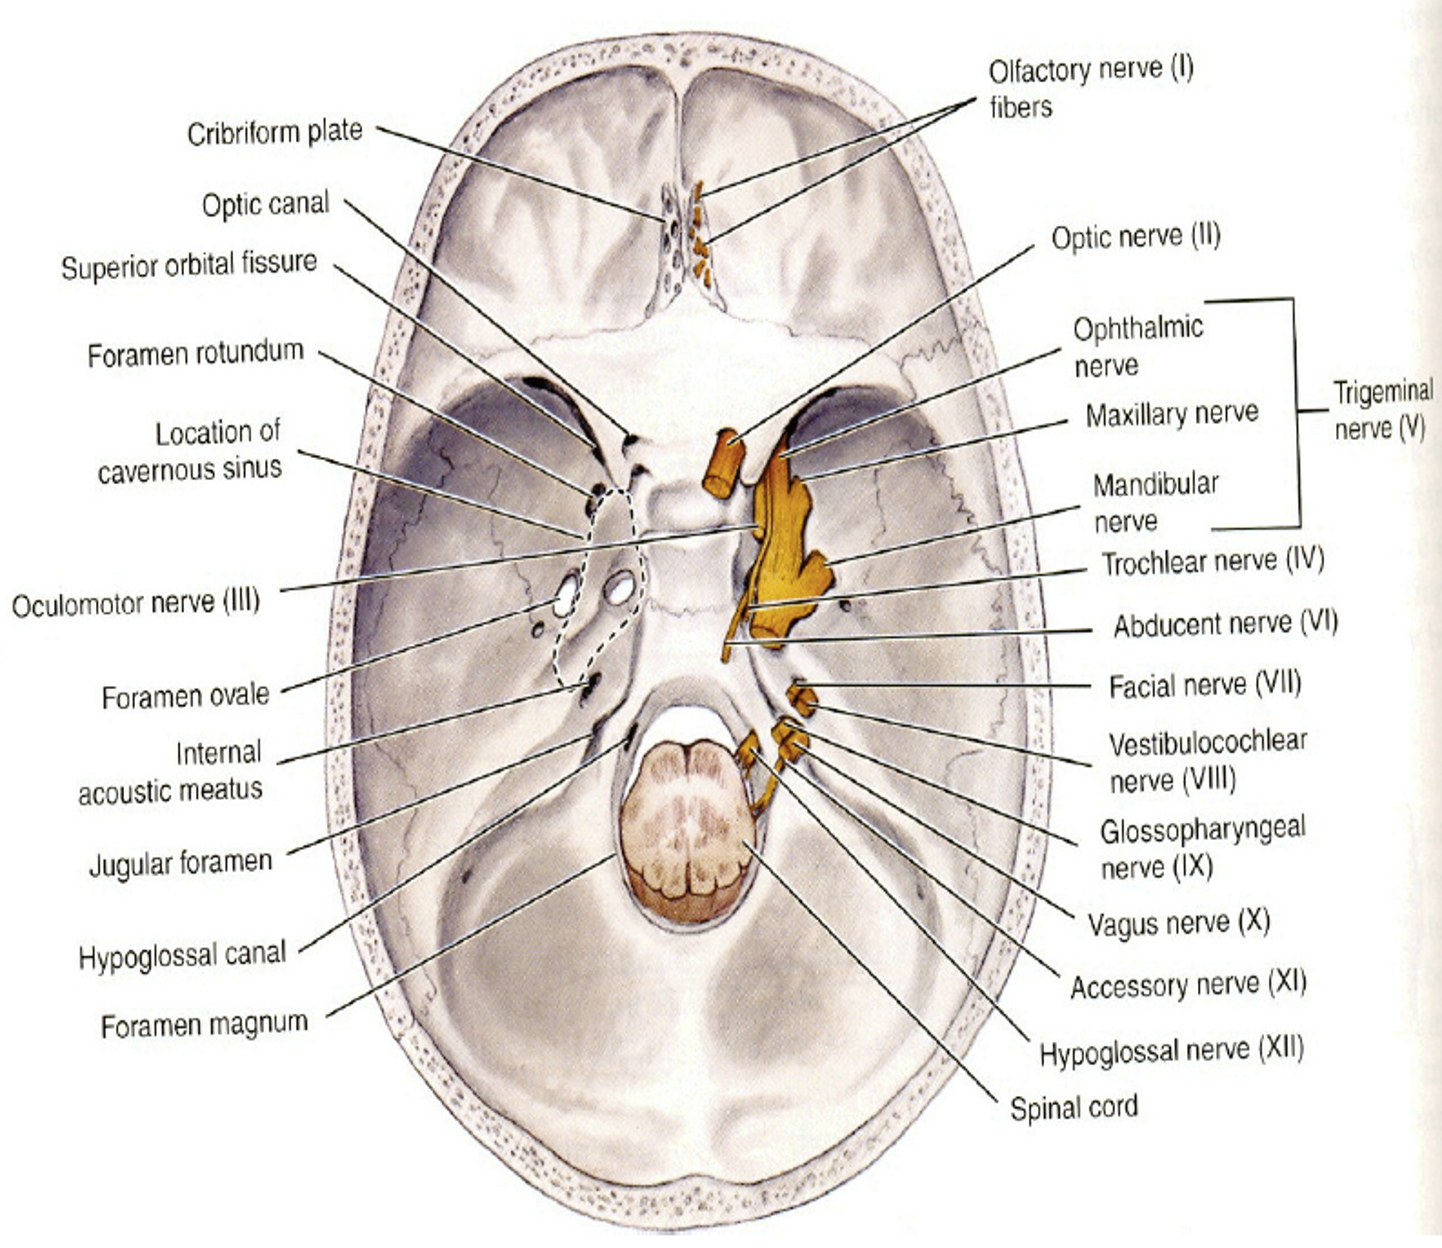

Nerve

Info

感覺神經 1, 2, 8

運動神經 3, 4, 6, 11, 12

副交感 3, 7, 9, 10

| CN | Origin | foramen |

|---|---|---|

| I | 嗅球 | cribriform plate |

| II | Optic Chiasma | optic canal |

| III, IV | Midbrain | sup orbital fissure |

| V1, VI | pons | |

| V2 | foramen rotundum | |

| V3 | foramen ovale | |

| VII | Internal coustic meatus | |

| VIII | Pons, Medulla 之間 | |

| IX, X, XI | Medulla | jugular foramen |

| XII | Hypoglossal canal |